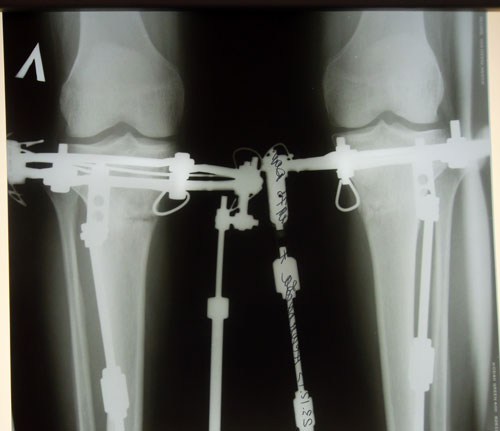

Перед крутками.

Деформация левой ноги больше на 10 градусов.

SAM_6739.JPG